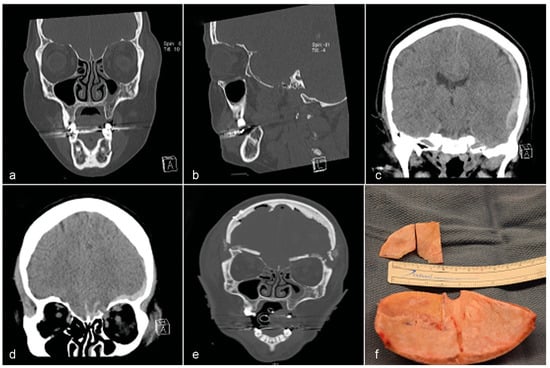

:Case 1